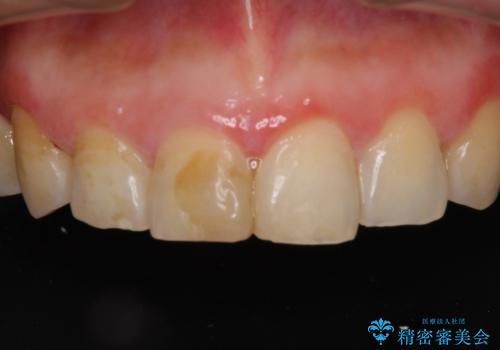

前歯のブリッジの見栄えが悪い→見えないところからしっかりとやり直しを

一見きれいにはいっているセラミックも、はずして中の状態をみるとひどいことが多い。これは、中の土台の状態や処理のクオリティは、短期的には問題を起こしづらく、患者さんには見えない部分だからです。

かぶせ物の種類:PFZ standard